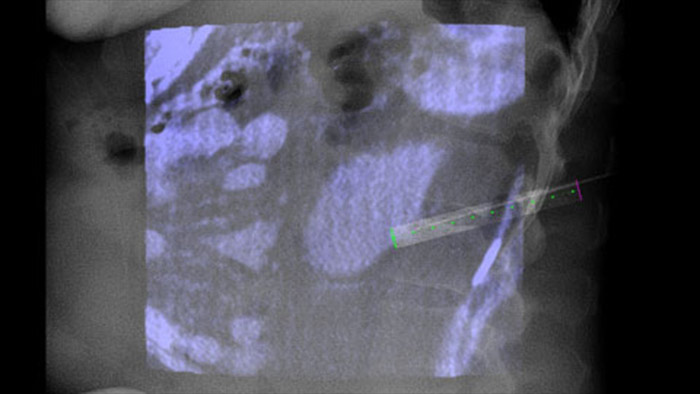

XperGuide proporciona una guía de imagen en vivo de alta precisión de cada aguja a una posición determinada mediante la superposición de trayectorias preplanificadas con imágenes fluoroscópicas.3

Adquiera una CBCT posterior a la ablación para demostrar la extensión de la cobertura del tumor y confirmar la finalización de su tratamiento.